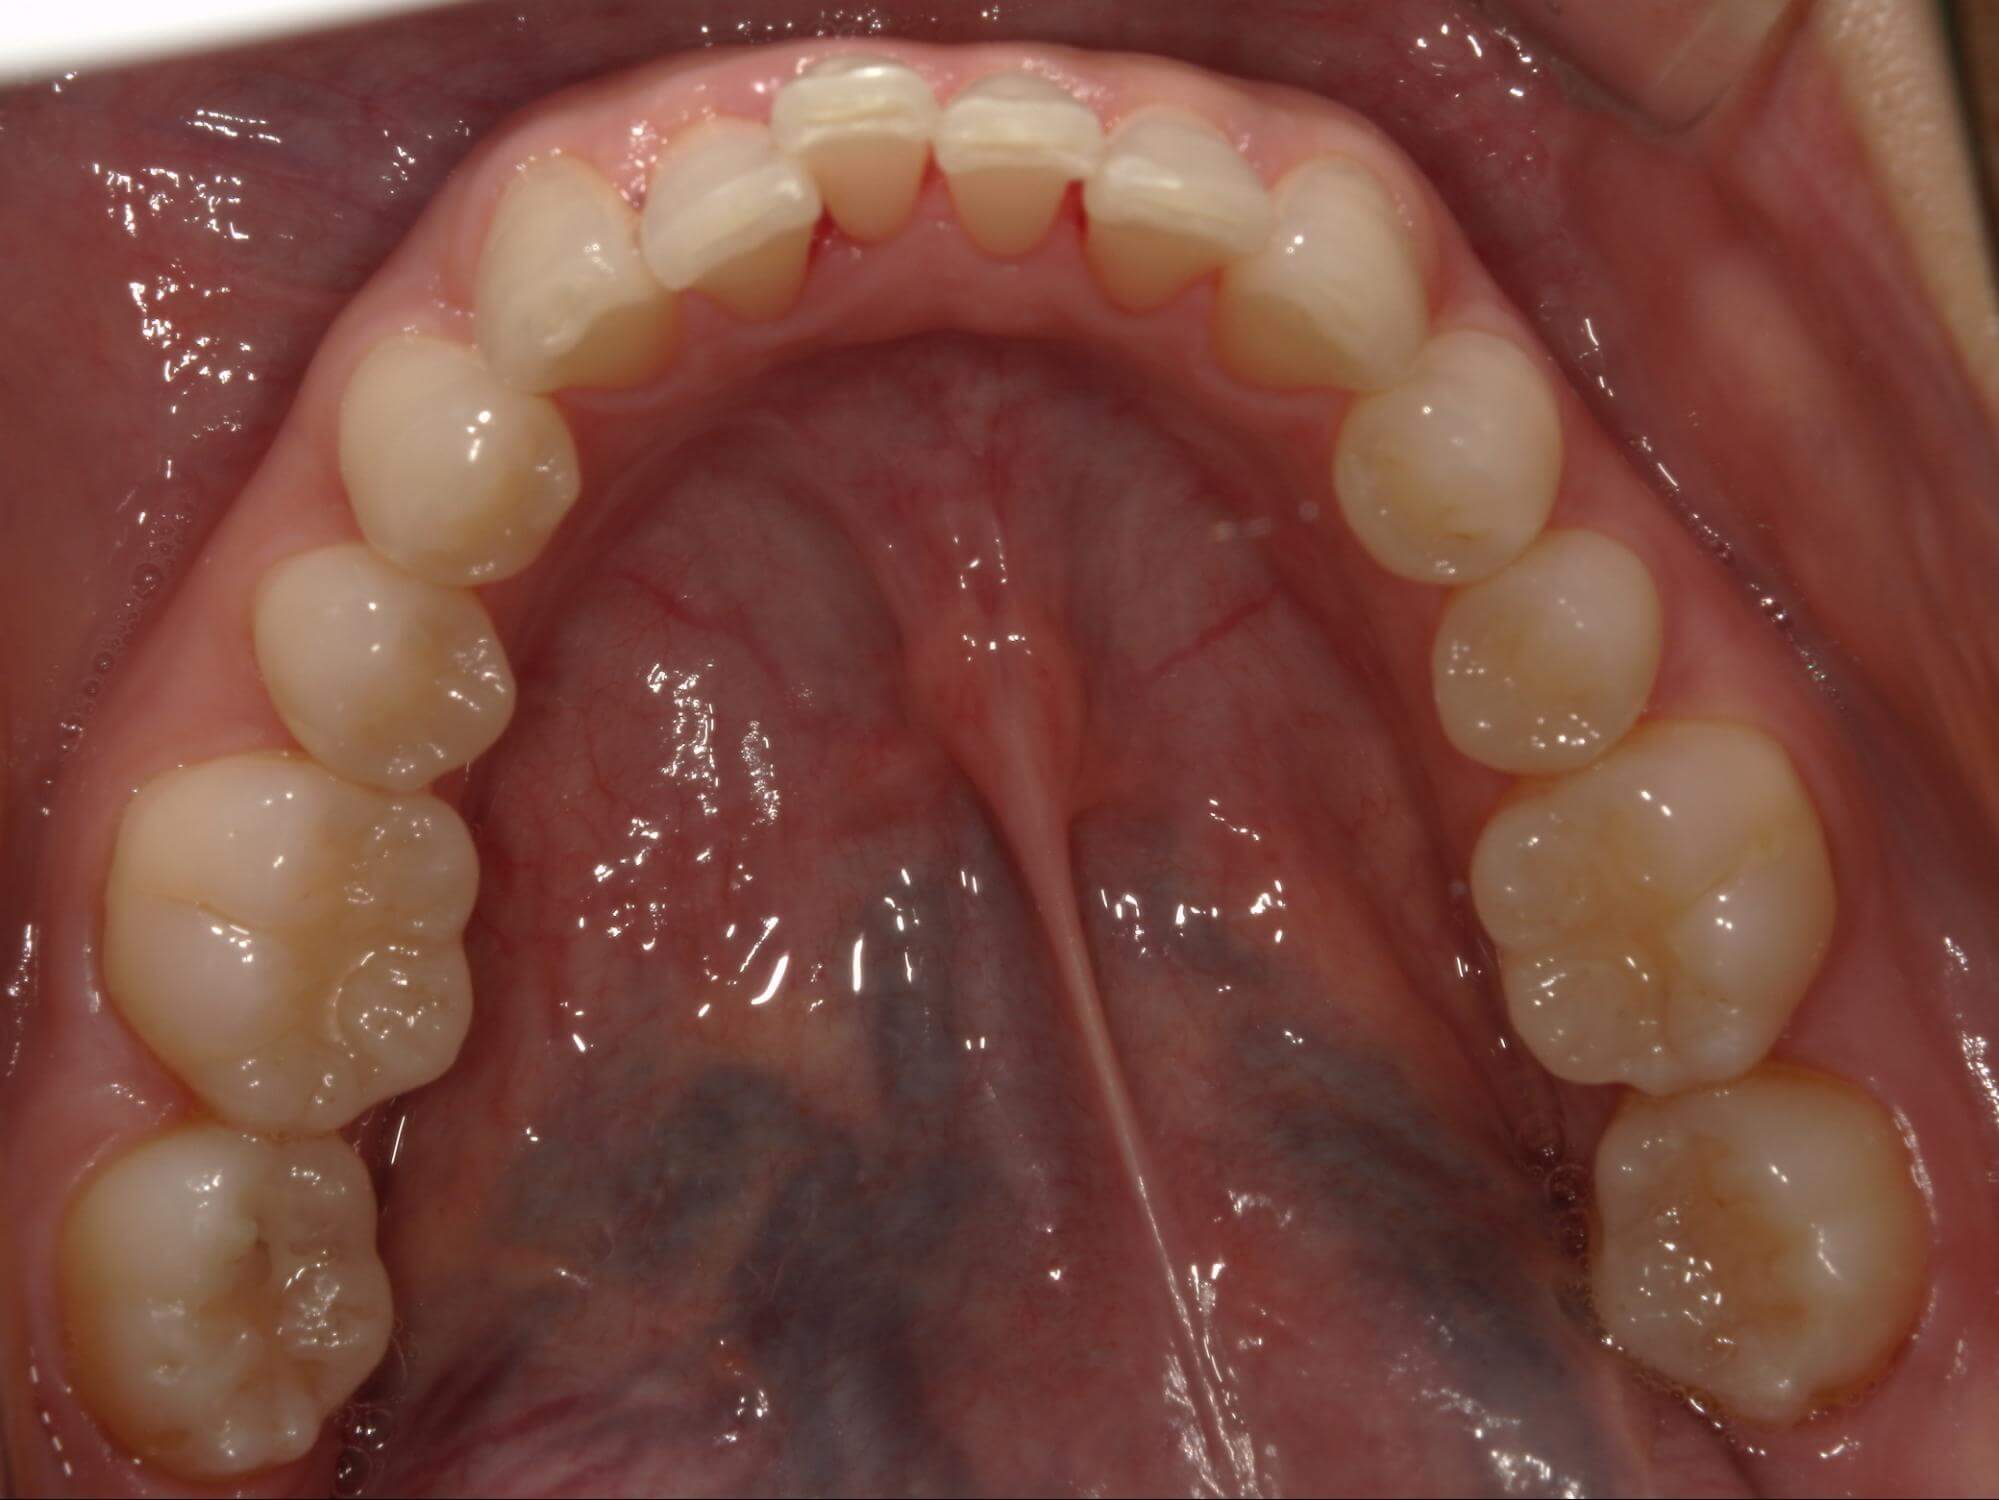

| 年齢・性別 | – |

|---|---|

| 主訴 | 叢生が気になる |

| 治療期間・回数 | 2年 |

| 費用 | 935,000円 |